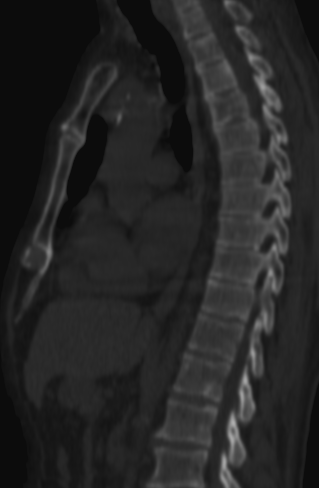

5. Multiplex bone metastases. Bone scintigraphy, anterior (a) and posterior (b) whole body scans. SPECT-CT sagittal plane, fusion image (c) and CT image (d). Obvious bone structural changes cannot be identified on the CT scan yet.

The examination is appropriate for staging a malignant process and following-up bone metastases. It is clinically most suitable for lesions that frequently present bone metastasis, primarily in case of prostate-, breast-, lung cancer and neuroblastoma. It is, however only indicated in cases where the soft tissue involvement of the tumor is big enough to suggest a higher incidence of bone metastasis; before radical surgeries and for the selection of patients who would benefit form a palliative radionuclide therapy. Otherwise, scintigraphy is advisable in case of any primary tumor, if the suspicion for metastasis is raised, e.g.: bone pain, pathologic radiological or lab results (elevated serum ALP and tumor marker levels). Bone metastases in most cases are located in bones that contain red bone marrow (skull, vertebrae, ribs, sternum, pelvic bones and the proximal bone segments of the limb) and usually show a multiplex appearance. Activity increase can be seen typically, metastases that cause activity decrease are rare; they could occur in cases of thyroid gland tumor, renal carcinoma, lymphoma and multiple myeloma. Solitary lesions or a few lesions only, due to the aspecific nature of the examination, cause a differential diagnostic problem in many cases, for example vertebral degenerative processes can mimic metastatic activity. Equivocal lesions usually require further, targeted radiological investigations. A negative X-ray examination does not rule out the possibility of a metastatic lesion, since the isotope scan is more sensitive. Therefore, it is possible that it could already be detecting an existing metastasis, while X-ray is still insensitive and unable to show the lesion. (Figure 5.)